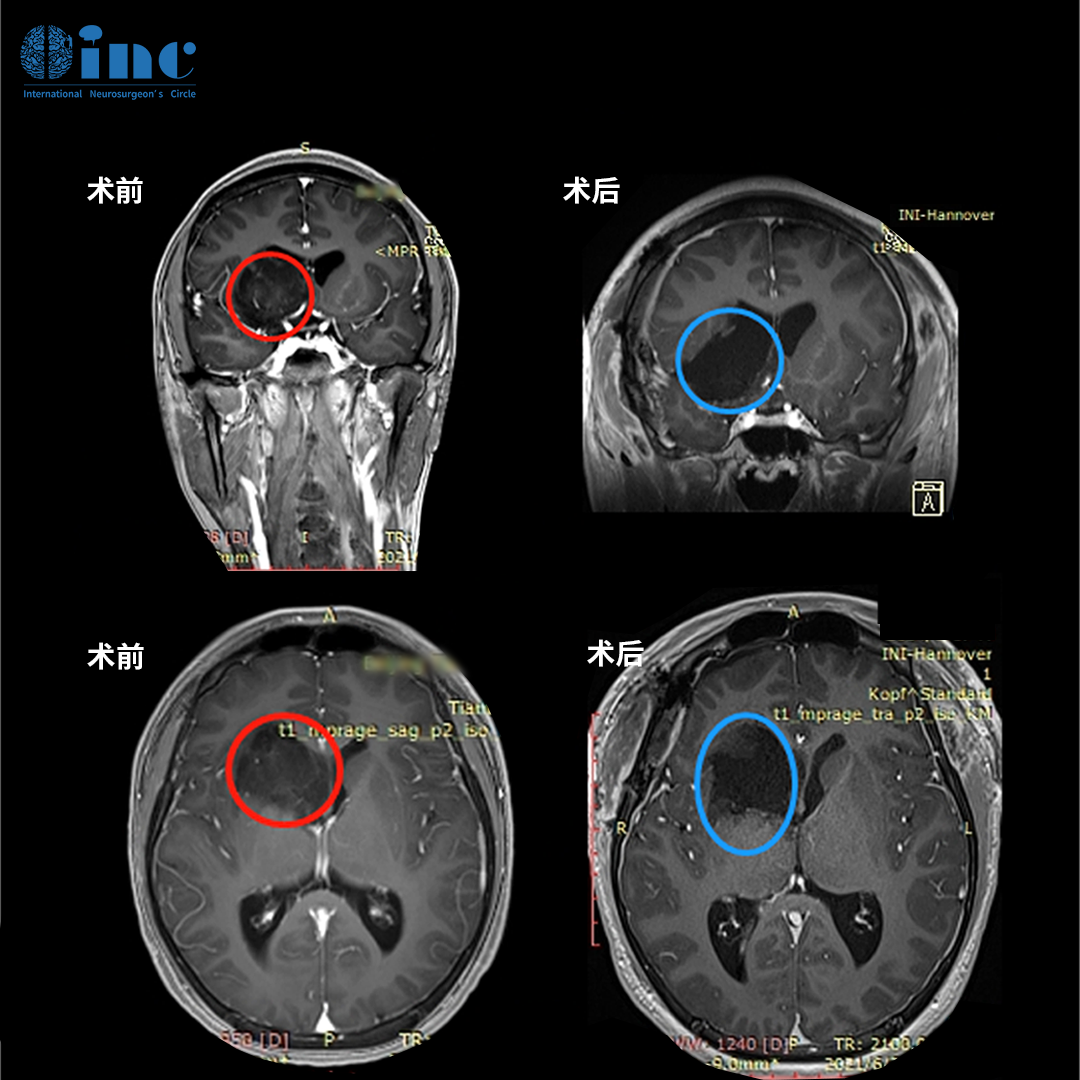

阿杰父母联系到巴特朗菲教授,并远程请求其对病情进行评估。幸运的是,巴教授认为阿杰可以接受手术治疗,切除率有望达到80%以上。"我们希望尽可能多地切除肿瘤,但同时保留患者的神经功能。"通过了解,阿杰父母得知巴教授在类似病例中取得良好术后效果,无额外神经功能缺损,这一点在评估时得到教授确认。

"学习暂停,我要先战胜它!"在父母鼓励和对巴教授的信任下,这位16岁少年最终决定接受跨国手术。抵达德国后第三天,阿杰被推入手术室。巴教授通过右侧额颞开颅暴露病灶,在保护神经功能前提下最大程度切除肿瘤,随后借助术中MRI对照进行显微外科肿瘤切除术。手术过程未出现并发症,最终实现肿瘤近全切。

手术当天,阿杰成功转入ICU。术后第二天,意识恢复清醒,无新发神经系统损伤,CT扫描显示正常术后表现,无脑出血及明显脑水肿,肿瘤占位效应解除。转回普通病房后,阿杰在康复治疗师指导下开始活动,父母欣喜地发现他很快能够独立行走。术后第三天,可以正常进食,精神状态良好。术后第十二天,顺利出院,出院时意识清楚、反应灵敏、定向准确、无新发神经功能障碍。